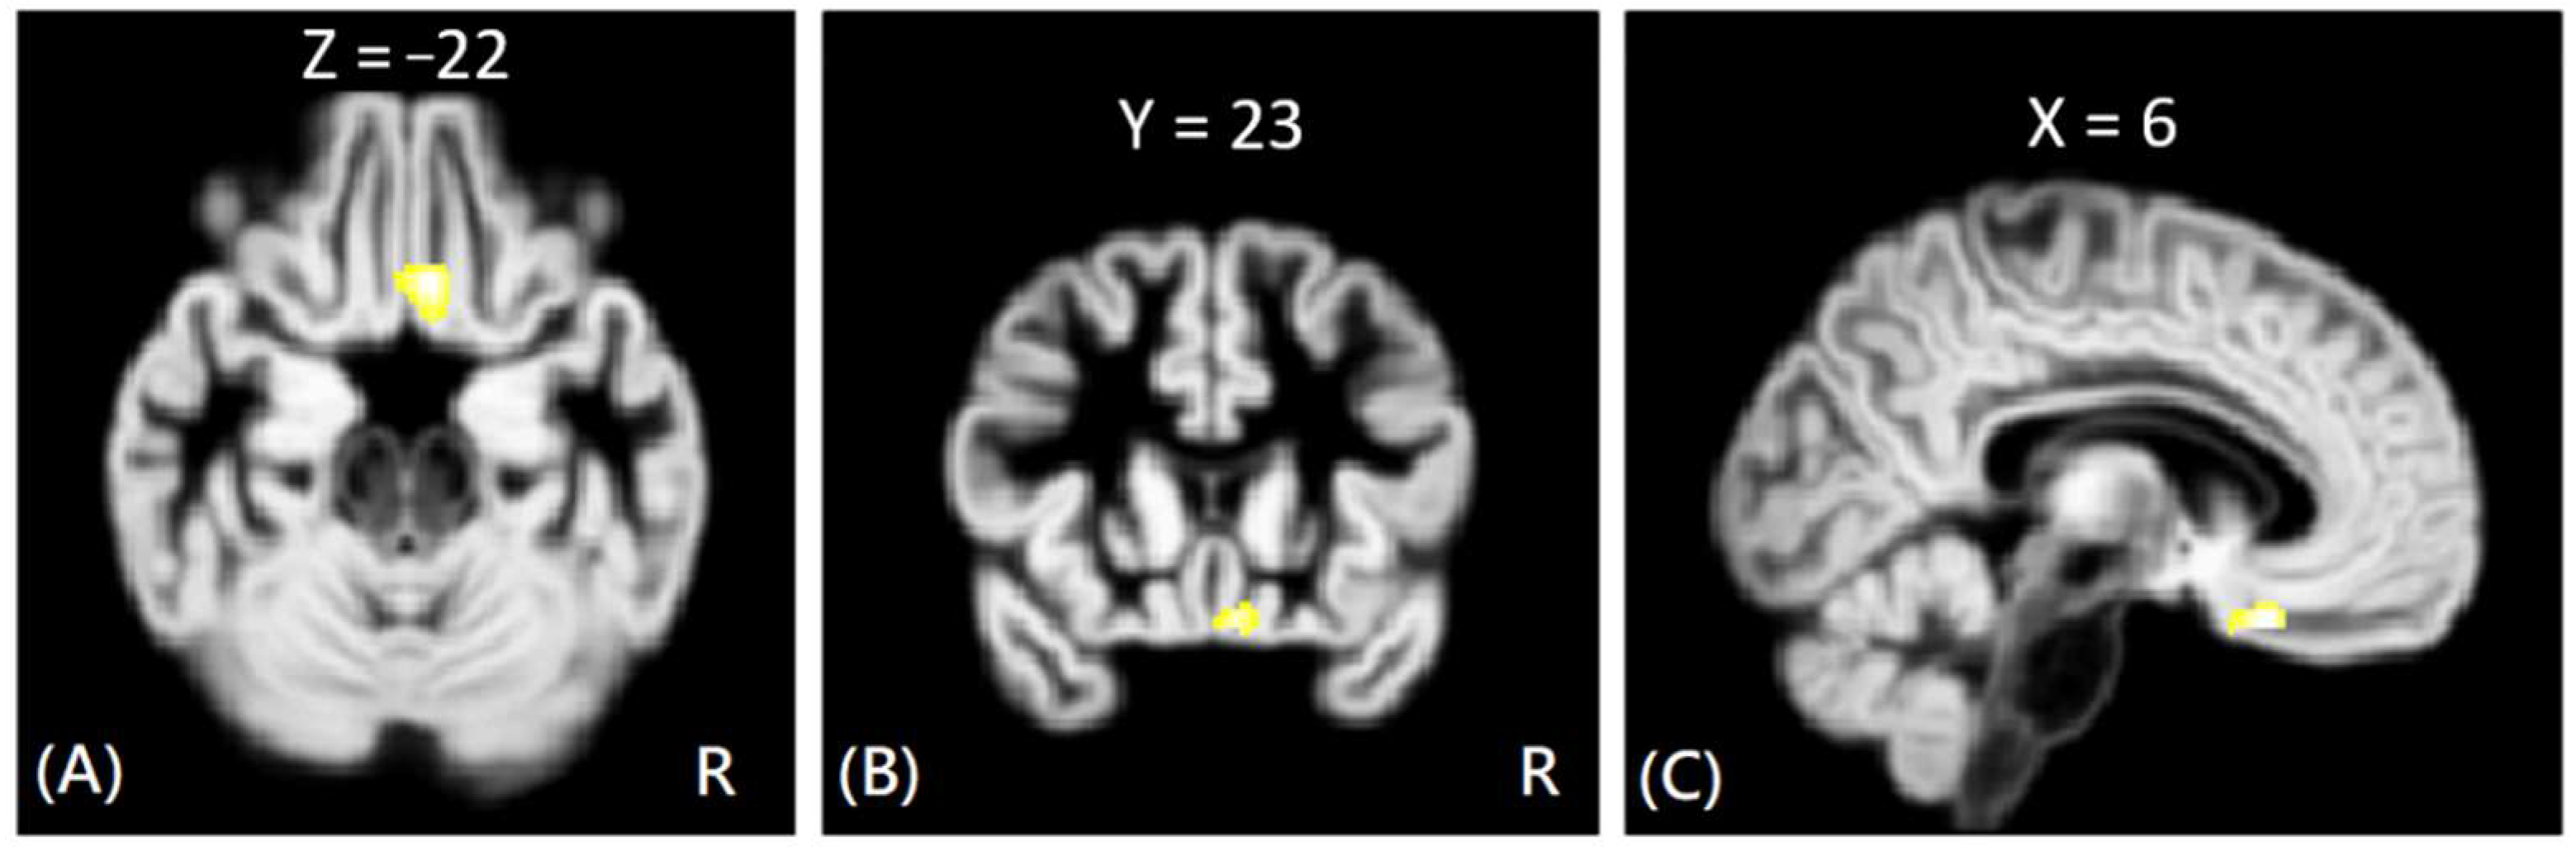

In VBM analysis, the results showed that the offenders (VA, VP, and NV) had significantly greater GM volumes than the HC group in the right superior temporal gyrus. The sub-group comparisons further revealed that only the NV group had significantly greater GM volumes than the HC group in the right superior temporal gyrus, but the VA and VP groups did not exhibit significant change in GM volume as compared to the HC group, as shown in Figure 1. In addition, the NV group had significantly greater GM volumes than the VP group in bilateral thalamus, whereas the VP group had significantly greater GM volumes than the VA group in the right middle frontal gyrus. However, no significant differences in GM volume were noted between VA and NV groups, as shown in Figure 2. The Montreal Neurological Institute (MNI) coordinates of regions with significantly different GM volumes between VA, VP, NV, and HC groups are listed in Table 2. No significant correlation was noted between GM volume and psychological scores in significant regions.

Figure 2. The VBM analysis of GM volume between the VP, VA, and NV groups. The yellow-white color indicates the significantly different GM volumes between VP and NV in the bilateral thalamus (AC), and between VA and VP in the right middle frontal gyrus (DF). The images are shown in axial (A,D), coronal (B,E), and sagittal views (C,F).

NV > VPLt. Thalamus−15−2053.82

Rt. Thalamus11−863.67

VP > VARt. Middle Frontal Gyrus3233423.98